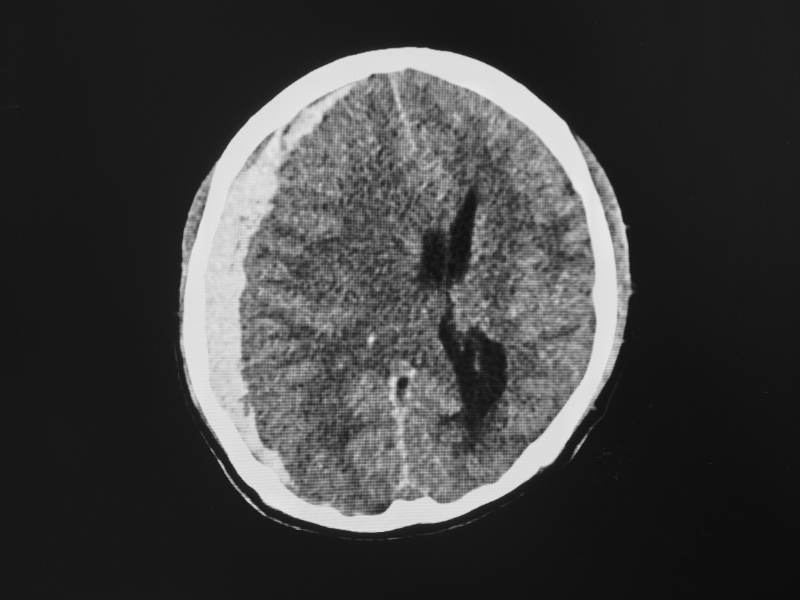

CT scans are typically the first imaging modality used in the acute setting of TBI. They are excellent for detecting acute hemorrhages, skull fractures, and mass effects due to swelling or edema. CT scans offer the advantage of rapid acquisition, being widely available, and offering good detection of acute bleeds and fractures. Unfortunately, they offer limited sensitivity for diffuse axonal injury (DAI) and small lesions and expose patients to ionizing radiation.

CT Showing Subdural Hematoma

A CT scan helps determine the degree of intracranial injury and helps predict the outcome. In those with normal CT scans, hospitalization may be avoided. CT scans help detect skull fractures, hemorrhage, midline shift, mass effect, and herniation. A repeat exam should occur in 4-8 hours for those with coagulopathies or intracranial hemorrhage. Abnormal findings on the CT scan, prolonged unconsciousness, persistent mental status changes, or an abnormal neurological exam necessitate referral to a neurosurgeon. Patients with normal CT scans after head injury will typically clinically improve within hours. Those who fail to improve should have a repeat CT scan (Rangel-Castilla, 2022).